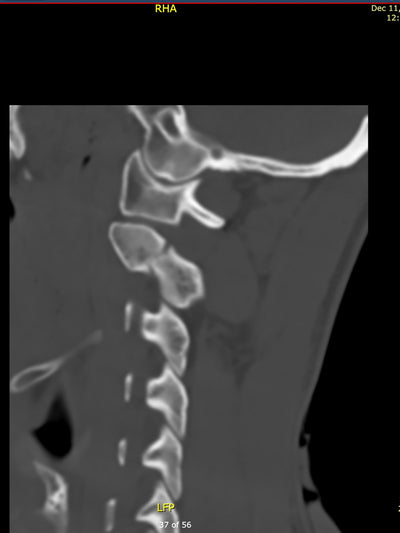

As soon as they saw the scan results, there was a sense of panic: My cervical vertebra C2 was fractured and I had to be hospitalized immediately.